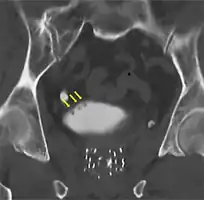

-

Bladder wall thickening due to cancer -